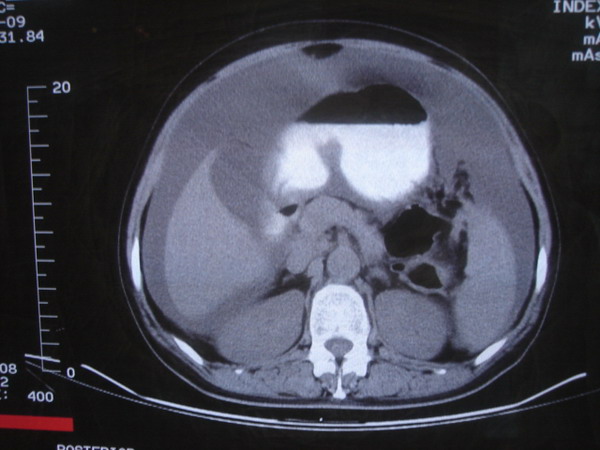

患者 女 52 腹部大量腹水。大家帮忙看看胃窦部有问题吗?

b超显示腹部、盆腔未见异常;化验室检查afp cea 正常,ca125 升高 347.4。

腹部大量腹水。胃窦部胃壁增厚,轮廓不规则!

1)不排除胃癌可能;建议行胃镜检查。2)大量腹水。

网膜不干净,可能为癌性腹膜炎。

腹部大量腹水。胃窦部胃壁增厚,轮廓不规则,胃癌待除外,建议胃镜检查。